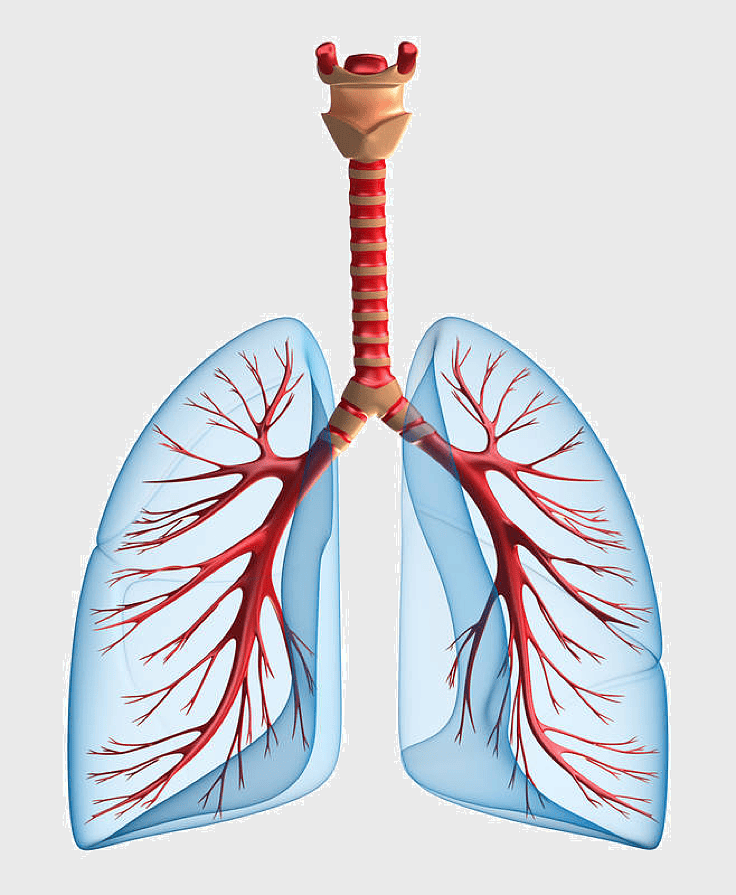

Pulmonary edema symptoms, chronic obstructive pulmonary disease diagram, kidney failure effects on lungs, pulmonary circulation illustration, lung disease diagnostic, respiratory health visuals, human anatomy respiratory system, PNG

- pulmonary edema symptoms

- chronic obstructive pulmonary disease diagram

- kidney failure effects on lungs

- pulmonary circulation illustration

- lung disease diagnostic

- respiratory health visuals

- human anatomy respiratory system

lungs illustration, respiratory system diagram, idiopathic pulmonary fibrosis, breathing anatomy, pulmonary health, respiratory tract function, lung disease awareness -

lungs illustration, respiratory system diagram, human lungs anatomy, pulmonary alveolus structure, bronchial tree visualization, trachea and bronchi, lung lobes detail -

Respiratory system anatomy, human breathing process, pulmonary alveoli structure, respiratory therapist training, respiratory health education, lung function diagram, respiratory disease prevention -

human lung anatomy, respiratory system illustration, heart and lungs diagram, bronchus structure, pulmonary function, thoracic cavity, medical imaging analysis -

lung organ, small lungs, respiratory system, pink trachea, human anatomy, medical illustration, pulmonary health -